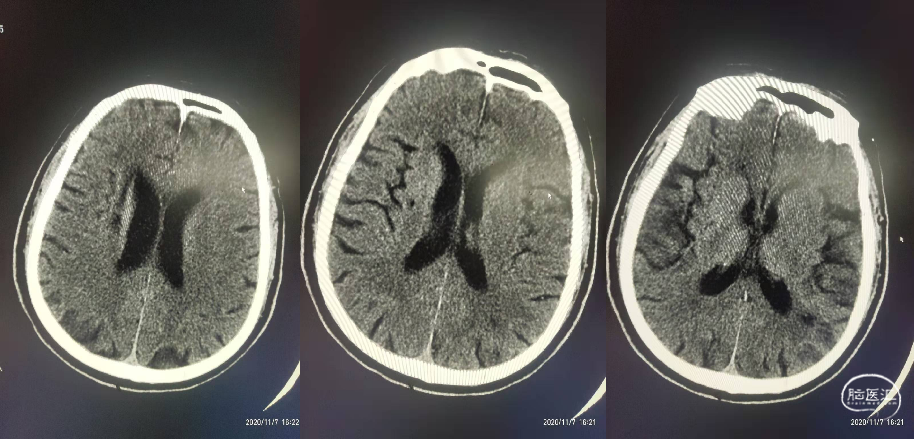

CT平扫:未见颅内出血及新发脑梗死。

DSA:Ⅱ型弓,左侧大脑中动脉M1段闭塞,左侧后交通动脉开放。

术后第二天复查CT左侧基底节区脑梗死。